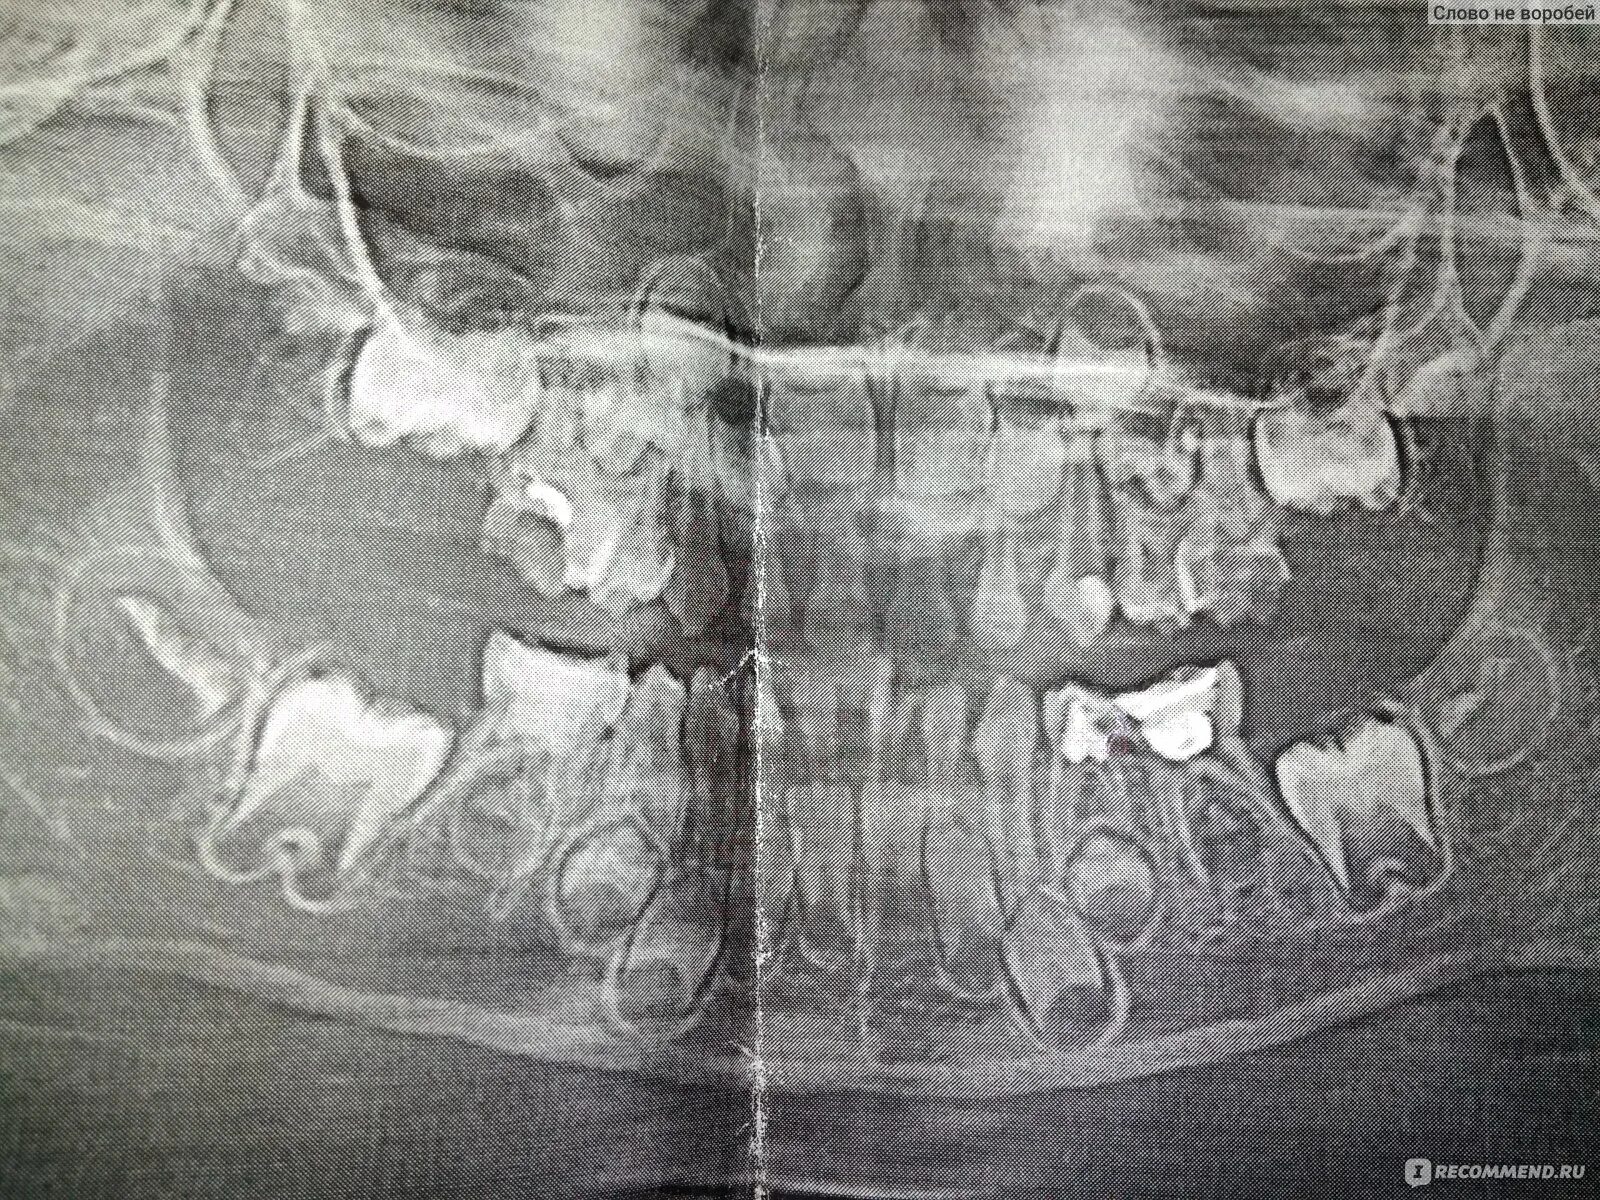

У ребенка нет зачатка постоянного зуба